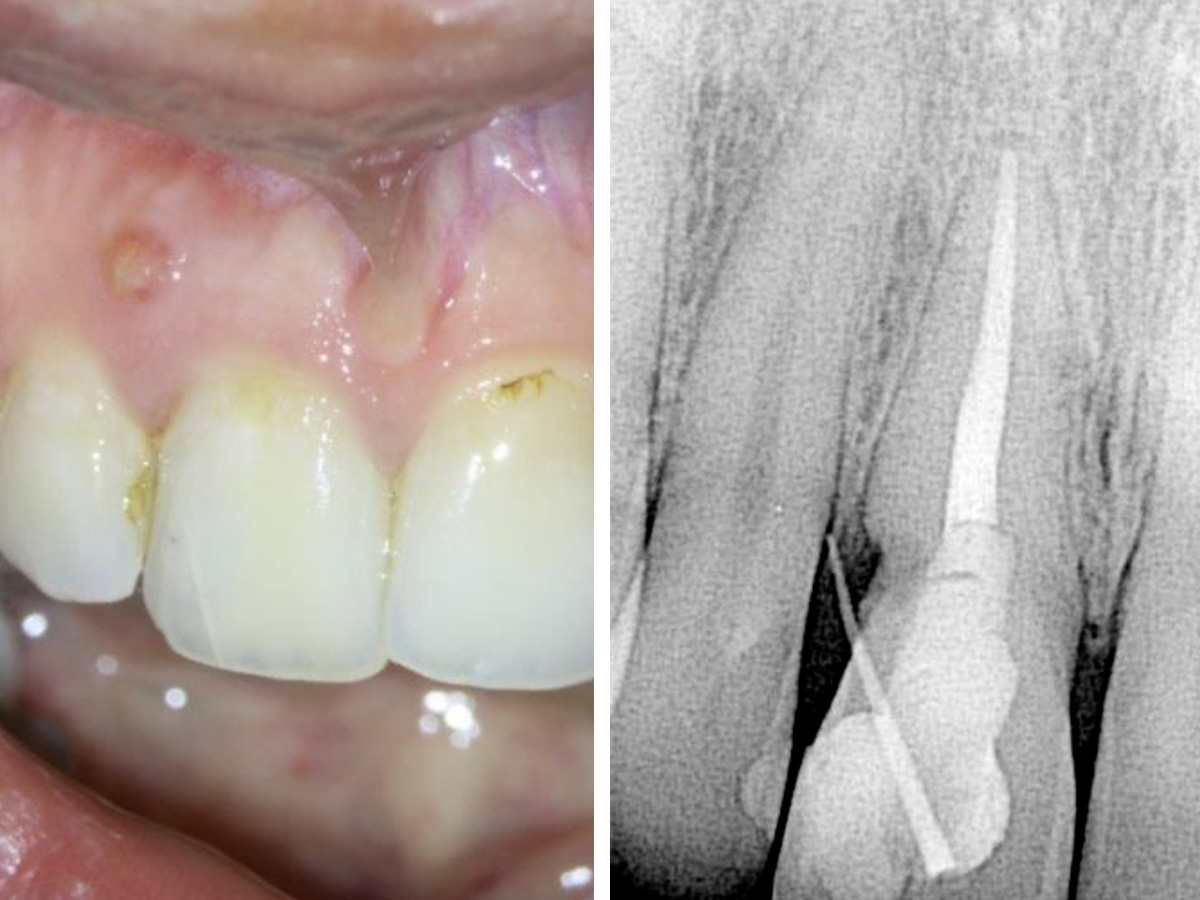

Abbildung 5

Die klinische Sondierung war normal und die Fistelöffnung verschwunden. Bei den Follow-Ups nach sechs bzw. 15 Monaten zeigten sich knöcherne Struk turen im resorptiven Defekt.

Bei den Follow-Ups nach sechs bzw. 15 Monaten war die Patientin noch immer symptomfrei. Die Sondierung war normal und es lag keine Fistelöffnung vor. Zudem waren knöcherne Strukturen im resorptiven Defekt erkennbar (Abb. 5).